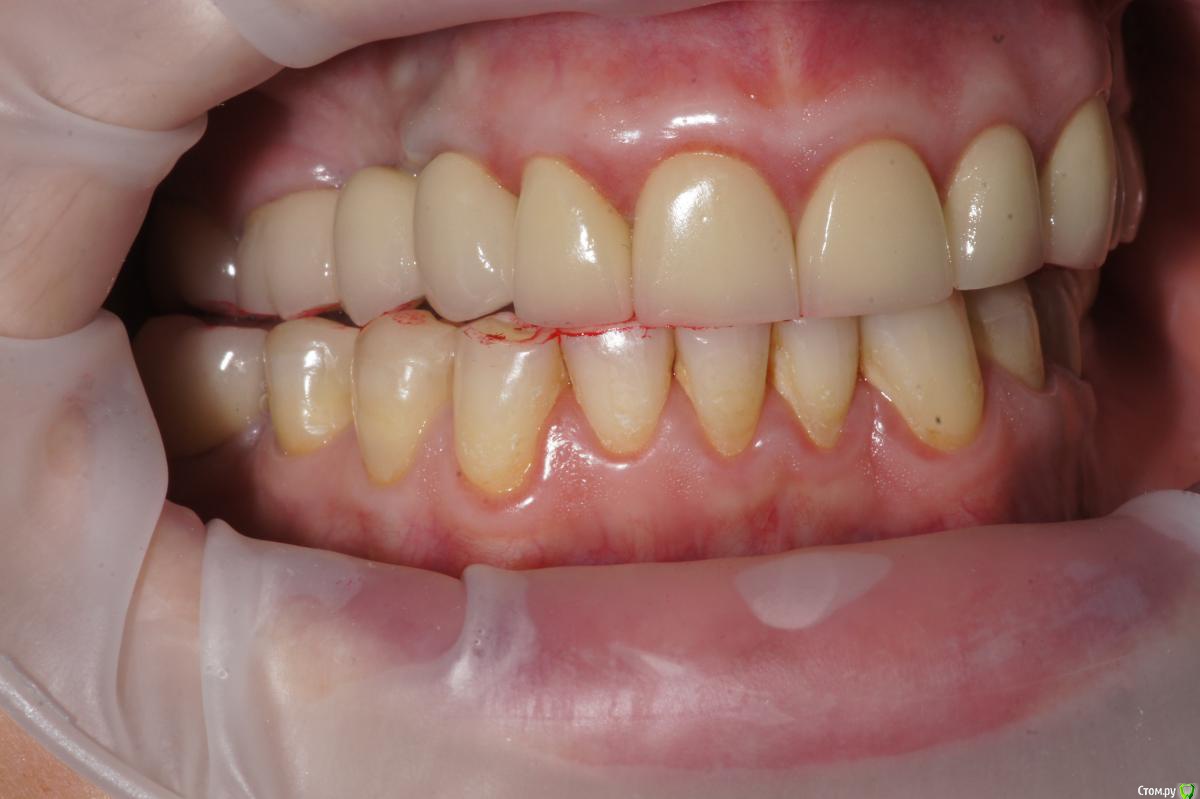

Alexandr_doc Опубликовано 21 сентября, 2018 Поделиться Опубликовано 21 сентября, 2018 Доброго всем времени! Пациентку протезировал доктор, которого уволили по ряду причин, обратилась ко мне на этапе после протезирования с жалобами на болезненность в области фронтальной группы зубов 1.2, 1.1, 2.1, 2.2, 2.3 при дотрагивании языком или пальцем. Перкуссия положительная как в вертикальном так и горизонтальном направлении. Установлены одиночные керамические коронки на каркасе из диоксида циркона. Отек, покраснение в области переходной складки отсутствует, также отсутствует болезненность при пальпации. Подвижность 1 степени. Прилагаю фотографии на этапе обращения. Ранее, на этапе протезирования было принято решение о депульпировании фронтальной группы тк присутствовала пульпитная симптоматика, после чего состояние улучшилось и остается стабильным по сей день. Предположил несколько причин оставшейся симптоматики: 1) несостоятельно проведенное эндо лечение - вариант отмел тк по прицельным снимкам и кт отсутсвуют очаги воспалительных процессов 2) некорректно изготовленные искуственные коронки ( глубокая поддесневая препаровка и агрессивный контур коронки ) 3) - окклюзионная перегрузка. Совместно с пацинеткой принято решение о снятии коронок во фронтальном отделе, была предупреждена о том, что возможно не получить хорошей динамики. С переменным успехом картина после нескольких корректировок временных коронок остается преждней. Болезненность на прежднем уровне, плюс по ходу наблюдения пришлось снять мост с опорой на уровне имплантатов, тк имели место быть воспалительные процессы в проекции имплантата 1.5. С удовольствием отвечу на все вопросы и приму любую критику. Ссылка на комментарий

Corsag21 Опубликовано 21 сентября, 2018 Поделиться Опубликовано 21 сентября, 2018 (изменено) Точно ли на кт нет изменений на корнях зубов? Мне на рентгеновских снимках что-то видится. жесткая каппа на верхний зубной ряд - я бы начал с этого.Нижние резцы устойчивы?Чем вам не нравится глубокая поддесневая препаровка? Десна выглядит также как и на интактных зубах НЧ.Как проверяется работа на предмет локальной перегрузки - не знаю, расскажите пожалуйста. Изменено 21 сентября, 2018 пользователем Corsag21 Ссылка на комментарий

Alexandr_doc Опубликовано 21 сентября, 2018 Автор Поделиться Опубликовано 21 сентября, 2018 Точно ли на кт нет изменений на корнях зубов? Мне на рентгеновских снимках что-то видится. жесткая каппа на верхний зубной ряд - я бы начал с этого.Нижние резцы устойчивы?Чем вам не нравится глубокая поддесневая препаровка? Десна выглядит также как и на интактных зубах НЧ.Как проверяется работа на предмет локальной перегрузки - не знаю, расскажите пожалуйста.На кт изменений нет, мне хотелось их найти, но нет. Мне будет не сложно сделать срезы и приложить их к посту, рассматривал некачественное эндо как один из первых причинных факторов. Жесткая капа какая? Какой дизайн и схему порекомендуете? Десна действительно сейчас выглядит также как и в других участках. При гипсовке в ЦС проверены: наличие первого контакта на фронтальной группе, проверена схема направляющих, распределение контактов на моделях. Ссылка на комментарий